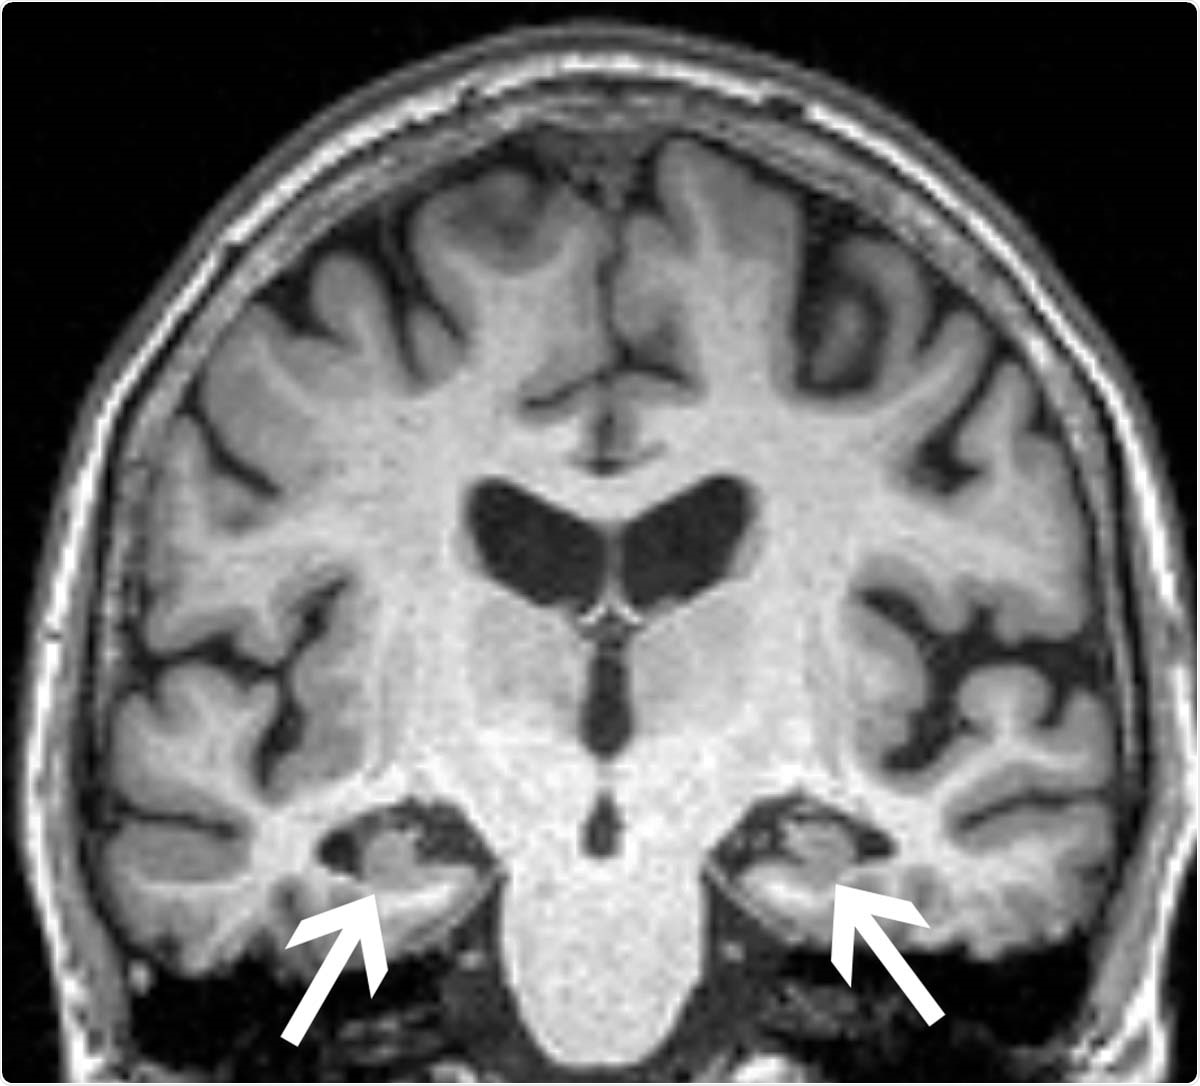

Brain MRI of a 72-year-old woman shows loss of volume of the hippocampus (arrows). The patient had all three characteristics, volume loss of the hippocampi, APOE4, and anxiety, found in the study to be associated with progression from mild cognitive impairment to dementia.

Image Credit: Radiological Society of North America